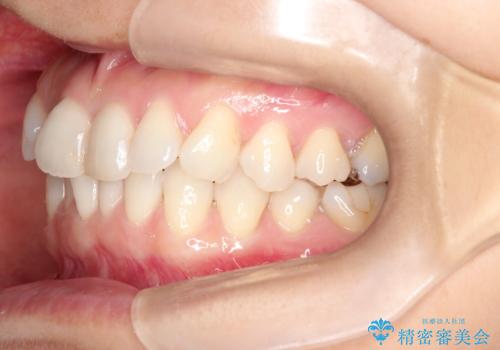

八重歯と前歯のガタガタをインビザラインで

- 八重歯と前歯のガタガタを主訴に来院されました。

目立たず矯正したいとのことでインビザラインで矯正することとしました。

インビザラインで目立たずに治療を終えることができ、喜んでいただけました。